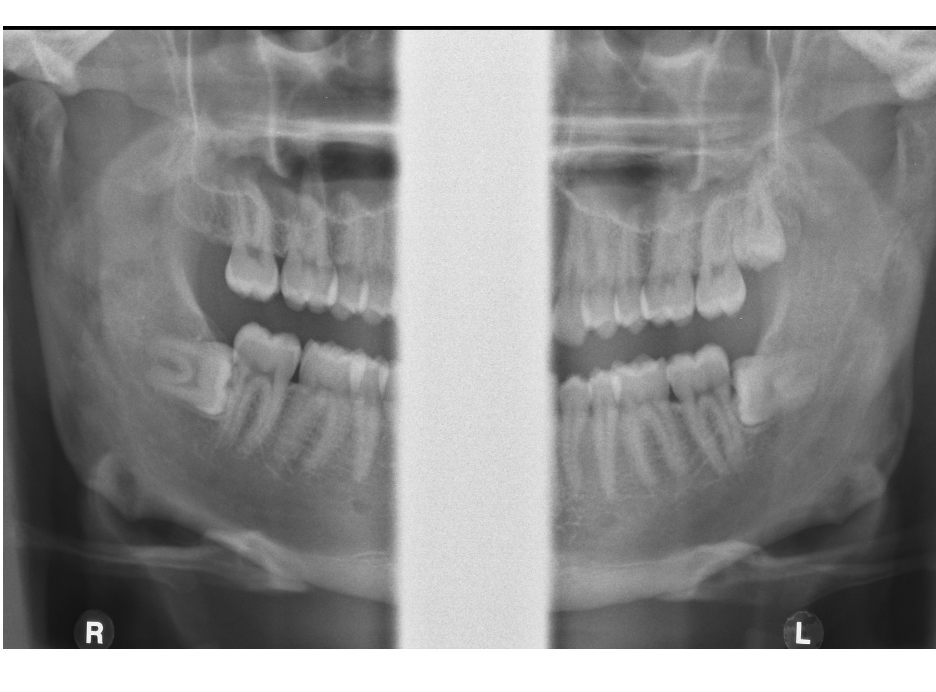

What can you observe in this radiograph?

What condition does this show?

Enlargement of pericoronal space

Chronic Pericoronitis

What do you see in this image?

Caries in both lower second molars

What type of impaction are these third molar?

Vertical

Right - Vertical

Left - Mesio angular